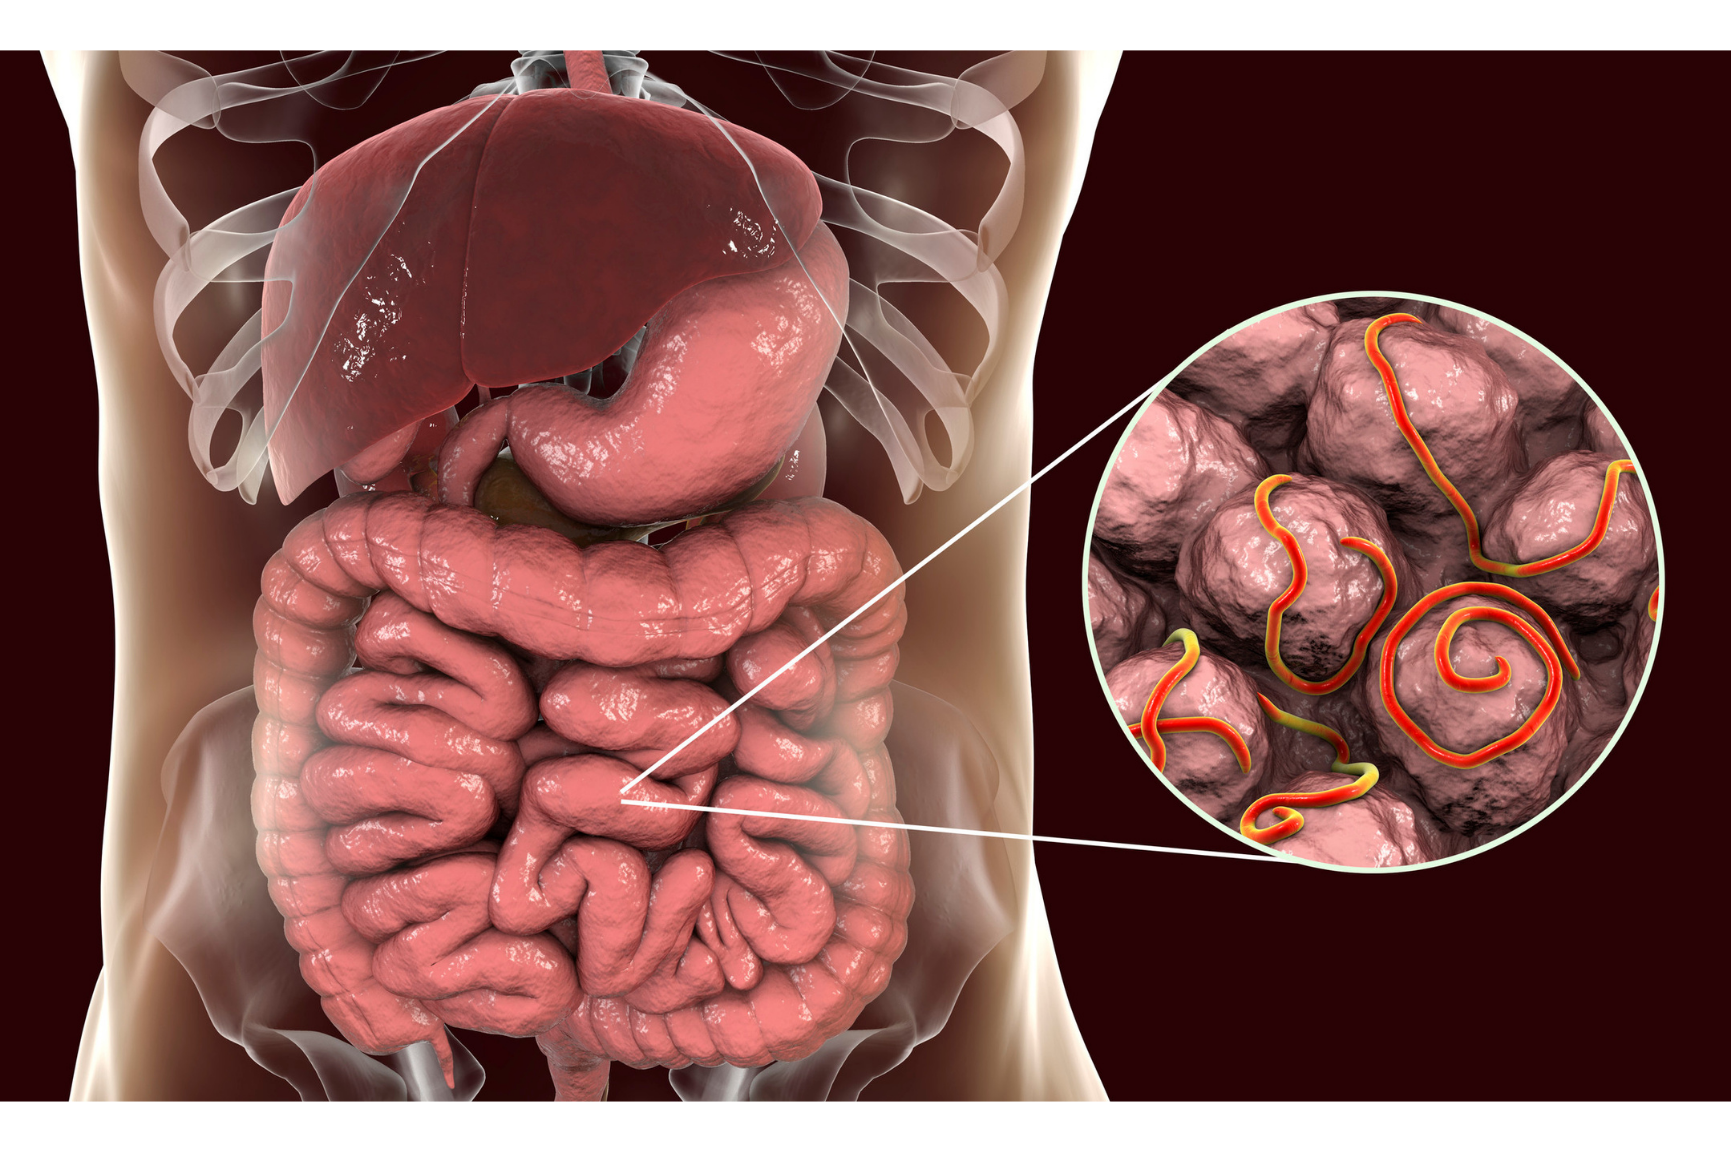

Gastroenterology is the field of medicine dedicated to the digestive system and the organs that support it — including your esophagus, stomach, intestines, liver, gallbladder, and pancreas.

These systems work together to break down food, absorb nutrients, and eliminate waste. When something goes wrong, it can affect everything from energy levels to immunity.

Gastrointestinal Conditions We Diagnose & Treat

From mild digestive discomfort to complex disorders, our team is equipped to manage and treat a wide range of GI issues with a personalized, evidence-based approach.

Some of the most common conditions we help with include: